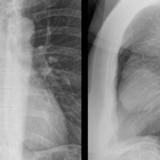

Case 1a

Thymoma

Date: 03/17/2004

Views: 4915

Case 1b

Views: 4921